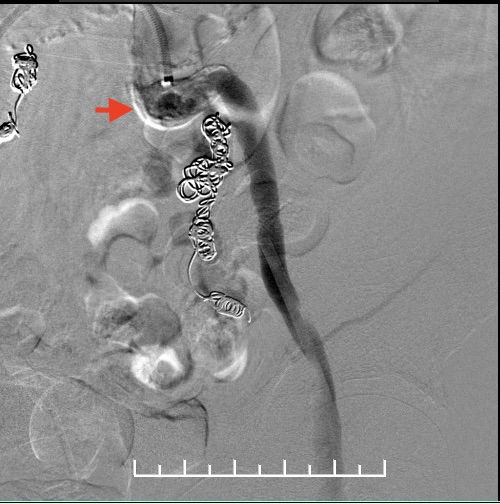

栓塞右侧髂内动脉,角度刁钻,使用翻山桥配合猪尾导管及超滑眼镜蛇,到达靶血管。8mm、6mm弹簧圈栓塞。

栓塞左侧髂内动脉。箭头处可见髂总动脉钙化扭曲明显,进出导管十分困难。